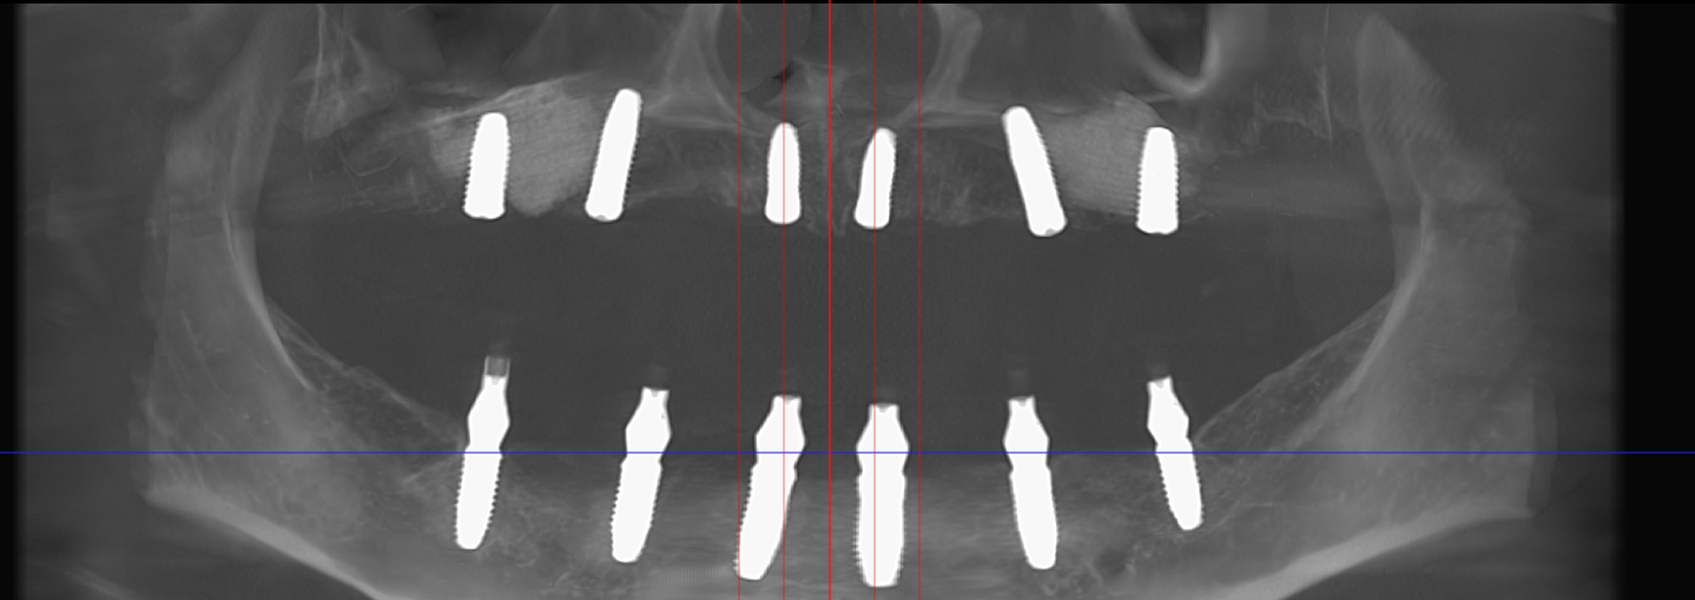

Metoda All-on-6 presupune inserarea chirurgicală a șase implanturi plasate strategic, pentru a asigura o proteză fixă stabilă și durabilă. Spre deosebire de conceptul All-on-4, recomandat în special pacienților cu deficit osos în zonele laterale ale maxilarului, All-on-6 are indicații mai largi și poate fi utilizat la majoritatea categoriilor de pacienți.

Această metodă este indicată pacienților cu edentație totală sau cu lipsuri dentare multiple, când dinții rămași nu mai pot susține o proteză fixă eficientă. Procedura se desfășoară în două etape:

- Investigație imagistică completă, ideal CBCT (computer tomografie);